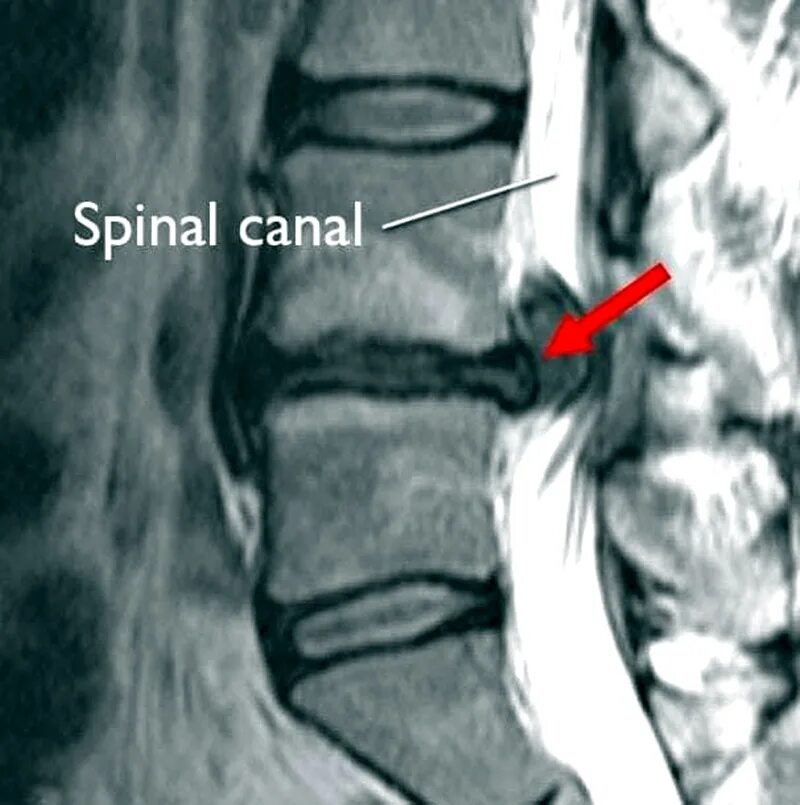

Как выглядит грыжа позвоночника на мрт